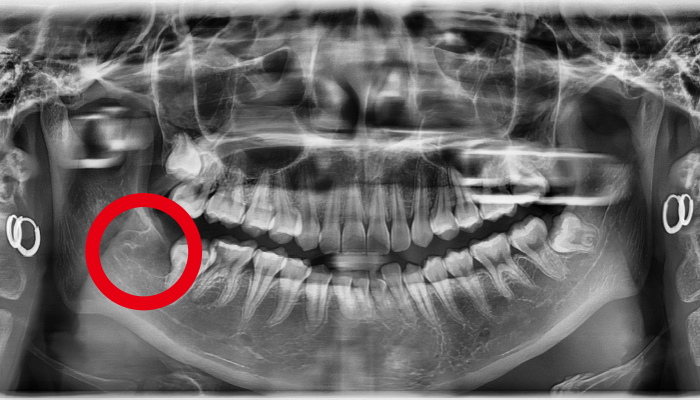

사랑니가 신경과 맞닿아 있는 상황을 제외하고는 안전하고 신속하게 발치가 가능합니다. 사랑니가 비스듬하게 누워있는 경우에는 수술적인 방법을 통해 발치를 해야합니다.

사람에 따라 다르지만 사랑니는 대부분 뼈의 자리가 부족하거나 기울어져 나거나 일부분에만 나오게 되어 관리가 매우 힘들고 인접 치아에 충치까지 유발할 수 있습니다. 매복사랑니는 고난이도 기술이기 떄문에 숙련된 의사의 발치가 중요합니다.

어금니 뒤쪽 공간이 부족하여 잇몸을 절개하여 사랑니를 발치하는 과정 중에 치아를 조각내거나 주위의 뼈를 갈아내고 뽑아야 하는 경우도 있습니다

사랑니 발치 전후 사례

• 치료전

치료후